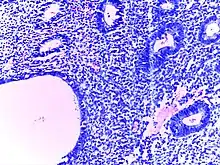

![]() | Adenocarcinoma colon | Micrograph of carcinoma colon showing malignant glands.Nuclei are small and vesicular, located at the bottom of the cell. The cells show increased nucleocytoplasmic ratio. | Category: Histopathology of colorectal adenocarcinoma | Colorectal carcinoma |